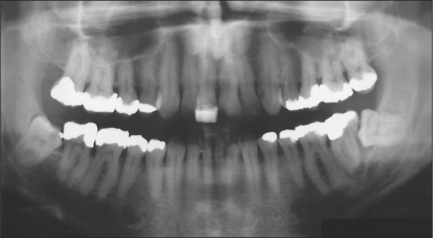

The following radiological assessment of the lower third molar should be made:

orientation (Fig. 5.4a), with particular reference to the distinction between vertical and distoangular

depth of the third molar below the occlusal plane (Fig. 5.4b)—the deeper the tooth the more difficult the surgery

the ratio of the distance between the distal aspect of the lower second molar and ascending ramus compared with the mesiodistal diameter of the third molar (Fig. 5.4c) (a ratio greater than 1:1 is associated with easier access)

image

Fig. 5.4 (a) Orientation of third molar: (i) towards second molar; (ii) away from second molar. (b) Increased depth of crown of right third molar (i) from occlusal plane compared to left third molar (ii). (c) Distance between anterior ramus and distal aspect of second molar compared with width of third molar crown: increased surgical access for right third molar (i) but reduced access for left third molar (ii).